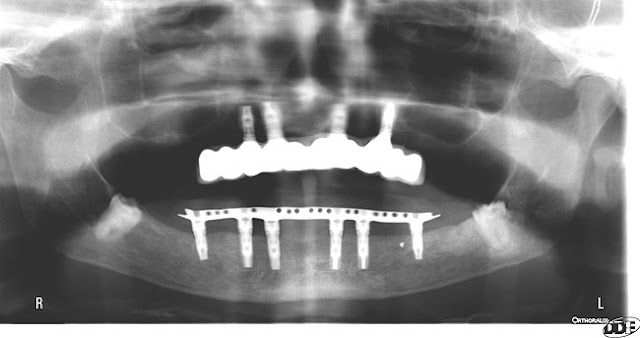

This lady spent probably around $80,000 and I guarantee she looks like she is 10-20 years older.

A primary contra-indication for a fixed maxillary implant supported prosthesis is severe anterior bone loss. Why? Well you can not have both a bulk of material to properly support the lip and make the restoration cleansable. In these types of cases either a Marius bridge or an overdenture is called for. Maybe the patient signed a form saying she would except a sunken lip in exchange for having something that she can not take out, but I doubt that. Now they wisely never show a face shot or profile shot, but you can see the significant loss of lip support in her lateral cephs. I immediately noticed the deficient lip on the cover and when I read the title I knew exactly why it was that way.

| Those implant are not distal enough to NOT angle them. #1 Why weren’t they angled as that is the protocol. #2 the left one could be placed more posterior by 4-5mm. |

This case would have been a slam dunk if the surgeon had placed implants where they should have been. It appears to me even if the restorative doc was presented with this case to start he should have insisted on an implant in #4 also, there appears to be room. They state in the article that she was class III to start with. I would like to see a lateral ceph because I am guessing she is class III because that is the pattern of bone loss. I also am guessing the lowers were restored right above the existing resorbed bone making it very difficult to restore the uppers properly (I do not know that for sure but is is highly likely and would fit with the poor planning pattern seen in this case). Against a mand implant supported prosthesis this case is at a much higher risk of failure.

These implants are placed far too distal. Ideal location is canine to lateral incisor. Premolar location creates a seesaw effect with the denture.